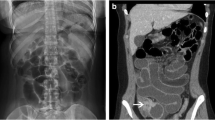

In each specimen, the mesentery of two standardised 40-cm lengths of bowel was dissected to expose the mesenteric arteries; the jejunal segment extended from 20 to 60 cm distal to the duodenojejunal flexure and the ileal segment from 20 to 60 cm proximal to the ileocaecal junction (Fig. 1). The following were recorded in each 40-cm length of jejunum and ileum in all ten specimens: the length of the mesentery (from the SMA to the mesenteric border of the mid-portion of bowel); the length of all jejunal and ileal parent arteries (branches from the SMA to the first arterial arcade); the total number of complete anastomotic rings within the arcades; the total number of arteriae recta. Each 40-cm length of jejunum and ileum was then divided into a proximal and distal section (each measuring 20 cm in length), and two further measurements were made: the minimum and maximum number of tiers of arterial arcades passed through in a straight line from the SMA to the bowel and the length of ten randomly selected arteriae recta (Carbon Fiber Composites Digital Caliper, Ted Pella, Inc., Texas; accuracy ±0.2 mm). All measurements of arterial arcades and arteriae recta were repeated blindly in two specimens by two investigators (DL and MDS) to assess intra-observer and inter-observer variability.

Comparison of mean jejunal and ileal parent artery lengths in each specimen showed no consistent differences. Although the overall mean length of parent ileal arteries (58.1 ± 36.9 mm) was greater than jejunal parent arteries (43.3 ± 13.1 mm), this difference was not statistically significant (p = 0.25). The number of tiers of arterial arcades in a straight line from SMA to bowel wall varied from one to three in the jejunum compared to one to six in the proximal ileal segment and two to four in the distal ileal segment. The mean numbers of complete anastomotic rings forming arcades in the 40-cm segments of jejunum and ileum were 9.4 ± 2.5 (range 7–14) and 24.7 ± 5.3 (range 12–31), respectively. This was a highly statistically significant difference (difference between means 15.3, 95% CI 11–19.6, p < 0.0001).

Our study suggested that jejunal arteries have a slightly greater diameter than ileal arteries in the mesenteric sections analysed. There was no evidence of a graded decrease in arterial calibre from the jejunum to ileum as suggested by Beaton and Anson (1942) from their detailed study of a single cadaver. Parent ileal arteries were not shorter than jejunal arteries as stated in one modern text (Floch 2005); although this might be expected because of the greater number of arterial arcades in the ileum compared to the jejunum, the longer ileal mesentery compensates for this. Our study confirmed the greater number of arterial arcades in the ileum compared to the jejunum; Beaton and Anson (1942) previously noted that the arcades were smaller in the ileum. We also found a significantly greater number of AR in an equivalent length of ileum compared to the jejunum, and these ARs were significantly shorter and narrower. The shorter AR length in the ileum has been reported previously (Dwight 1903; Cokkinis 1930; Noer 1943), but the neat progressive diminution reported by Cokkinis (1930) was not evident. Further, we could only find one previous report comparing numbers of AR in the jejunum and ileum, and this related to a single cadaver specimen (Beaton and Anson 1942); these authors also found a greater density of AR in the ileum than the jejunum. Chiba and Boles (1984) counted total AR numbers in the whole small bowel, and, interestingly, their figure of between 393 and 452 is remarkably consistent with our data. Finally, our novel data on the relative muscularity and elastin content of proximal jejunal versus distal ileal arteries and parent artery versus first arcade artery versus AR showed no significant differences in these mesenteric segments, except for the possibility of a higher elastin content in AR compared to their feeding vessels.